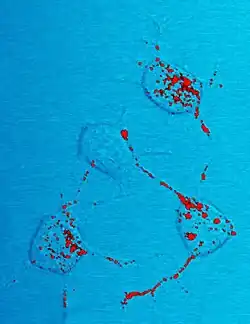

Prions cause neurodegenerative disease by aggregating extracellularly within the central nervous system to form plaques known as amyloids, which disrupt the normal tissue structure. This disruption is characterized by "holes" in the tissue with resultant spongy architecture due to the vacuole formation in the neurons.[77] Other histological changes include astrogliosis and the absence of an inflammatory reaction.[78] While the incubation period for human prion diseases is relatively long (5 to 20 years or more), once symptoms appear the disease progresses rapidly, leading to brain damage and death.[79][80] Neurodegenerative symptoms can include convulsions, dementia, ataxia (balance and coordination dysfunction), and behavioural or personality changes.[81][82]

Many different mammalian species can be affected by prion diseases, as the prion protein (PrP) is very similar in all mammals.[83] Due to small differences in PrP between different species it is unusual for a prion disease to transmit from one species to another. The human prion disease variant Creutzfeldt–Jakob disease, however, is thought to be caused by a prion that typically infects cattle (causing bovine spongiform encephalopathy) and that is transmitted through infected meat.[84]